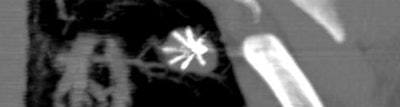

![]() |

| Above and below: Three-dimensional reconstructions of multidetector spiral CT datasets show correct placement of the radiofrequency needle into the tumor. Images courtesy of Dr. Riccardo Lencioni. |

The procedure was conducted under conscious sedation or general anesthesia, using an RFA device consisting of a 150-watt generator, temperature monitor, and expandable multitined electrodes (Starburst XL, RITA Medical Systems, Mountain View, CA).

"The concept was to destroy 1 cm of pulmonary tissue all around the tumor. This is why we deployed a maximum 5-cm (ablation target for) a lesion size of 3 cm" (1.0-3.0 cm, mean 2.2 cm ± 7), Lencioni said. "The RFA protocol, in terms of the time and temperature, was prolonged as much as 27 minutes to ensure full ablation of the 5-cm sphere."